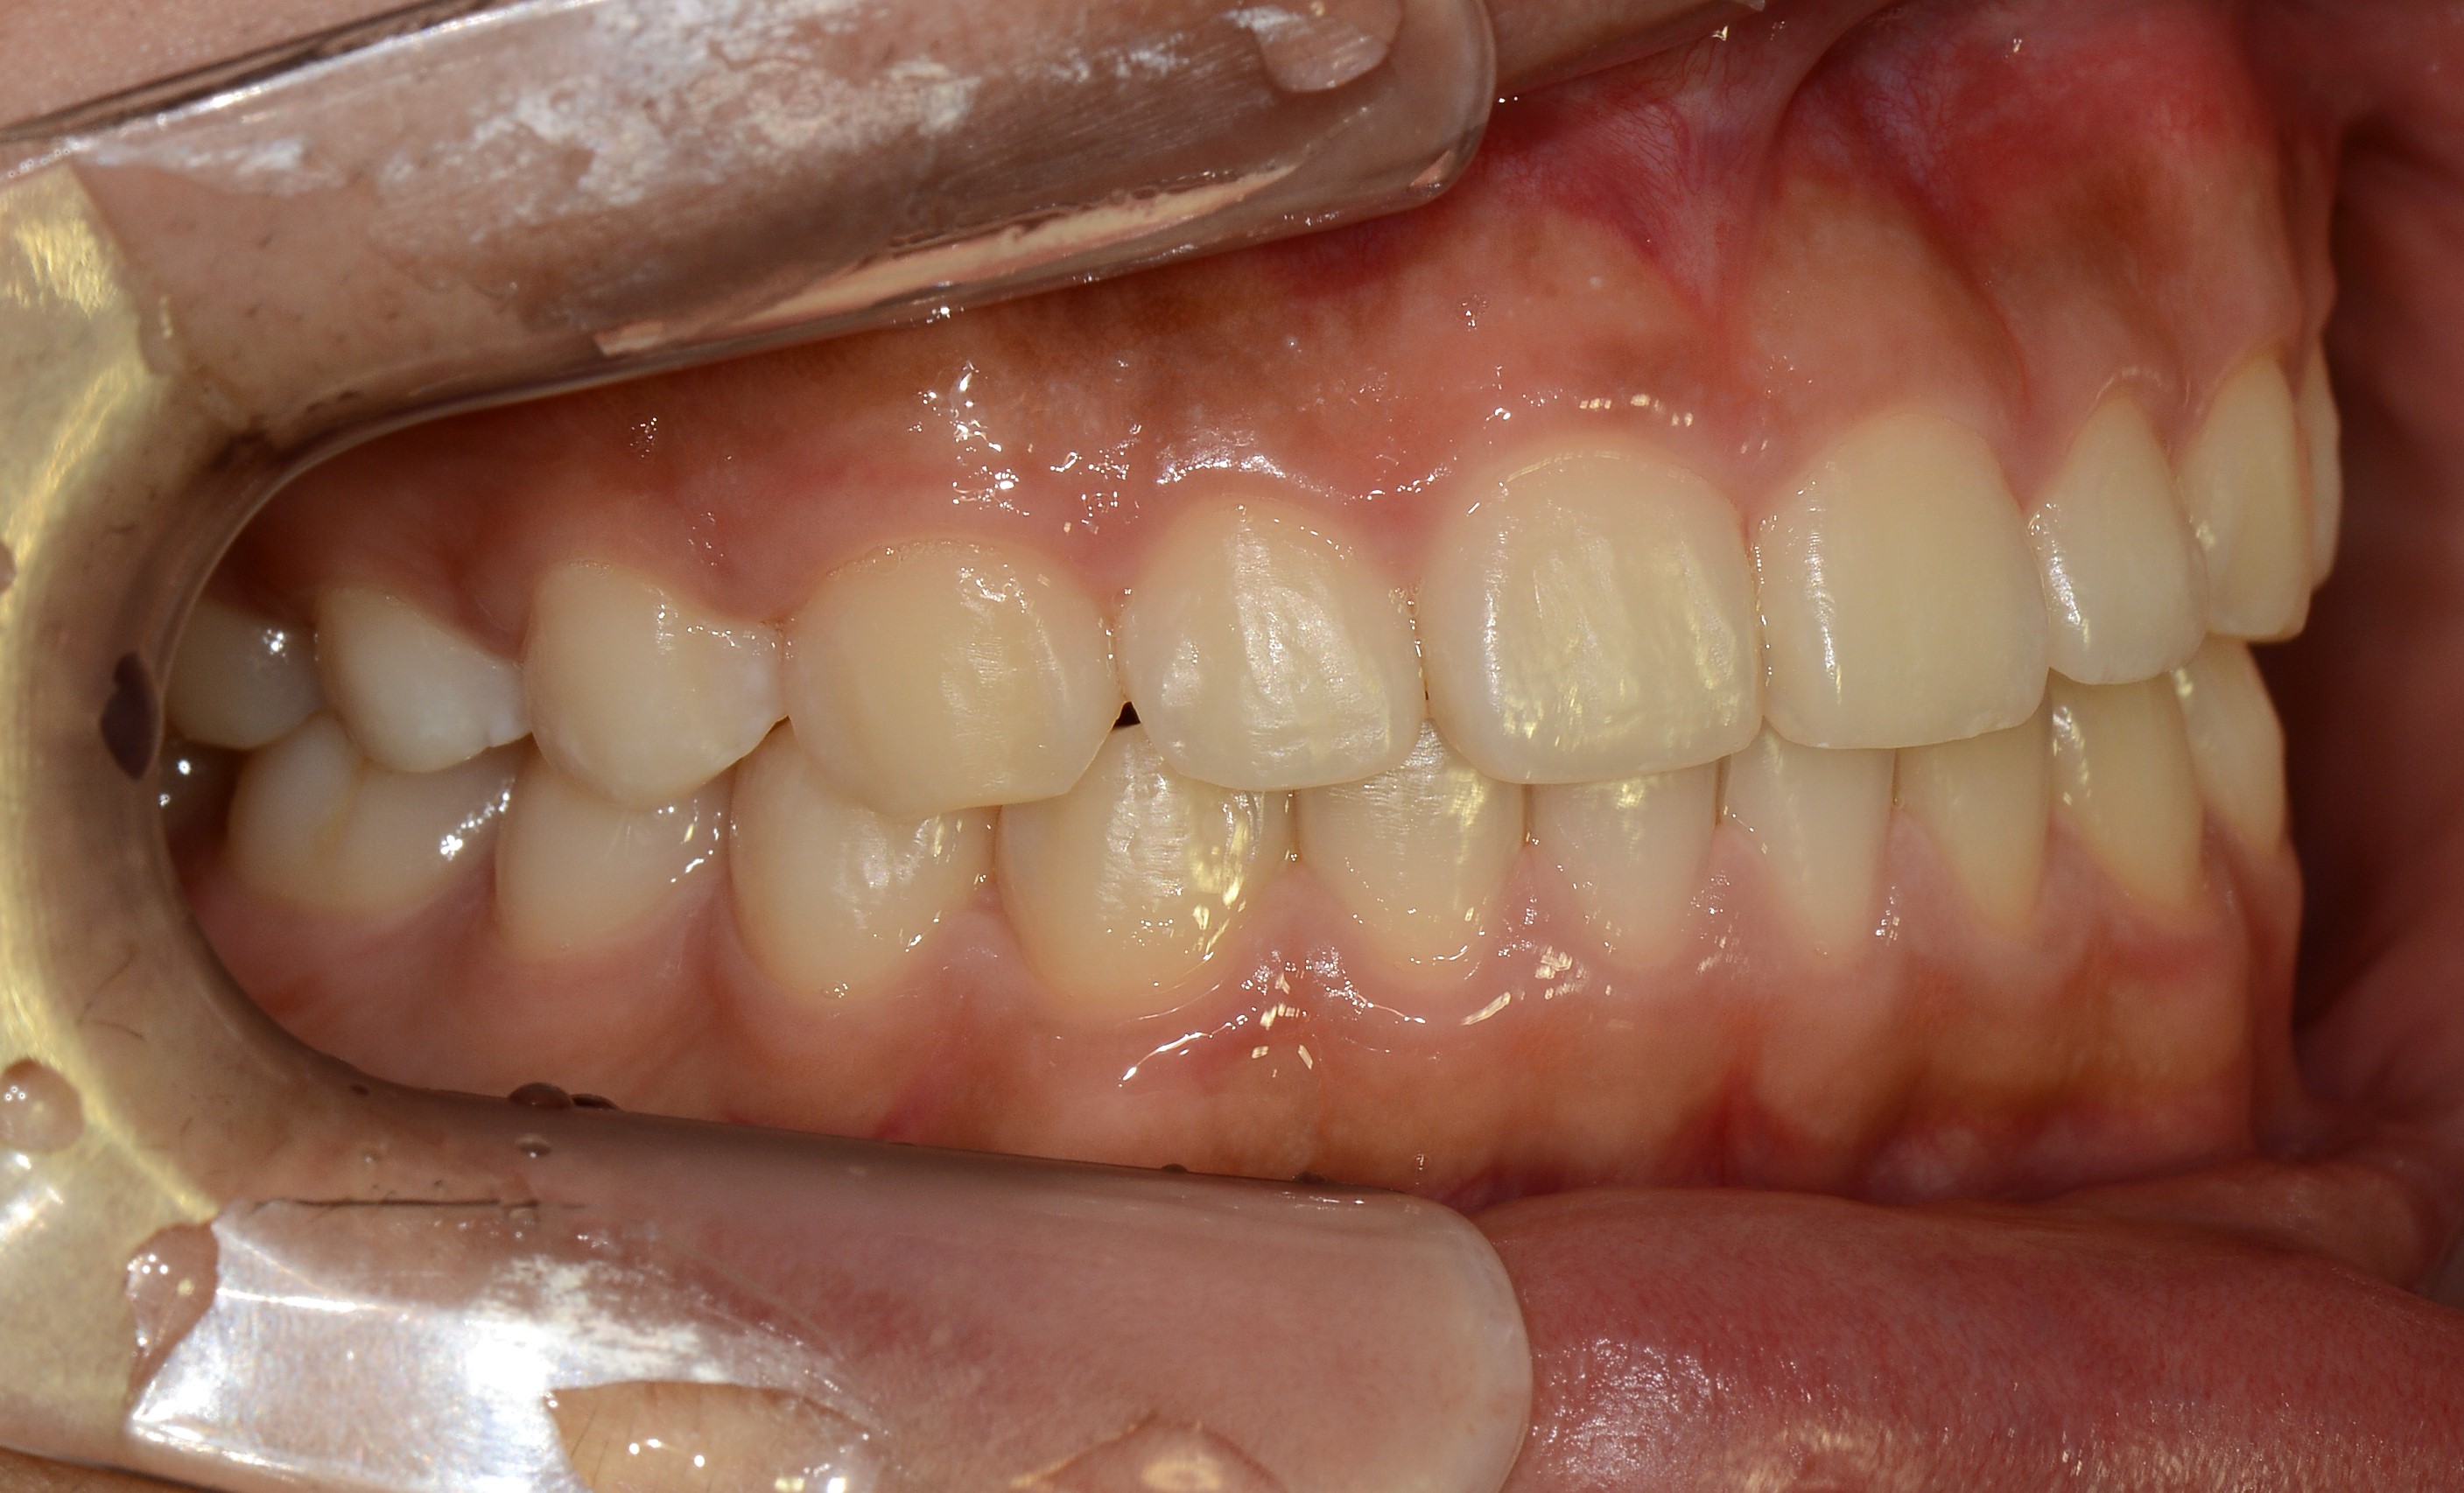

치료 전 사진입니다.